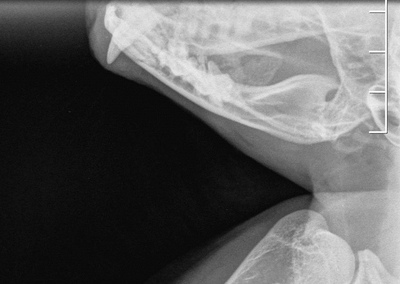

Вот как-то так выглядит кот напросвет. Теплоты там особо не видно, зато есть целый комплект косточек и перелом четвертой пястной кости.

Пока люди отвернулись, Линукс порвал сетку, вышел погулять на карниз и превратился в ракету класса "окно-асфальт". Жив, цел, орёл, месяц ходил со спицей в лапе, и всё равно умудрялся буянить по ночам.